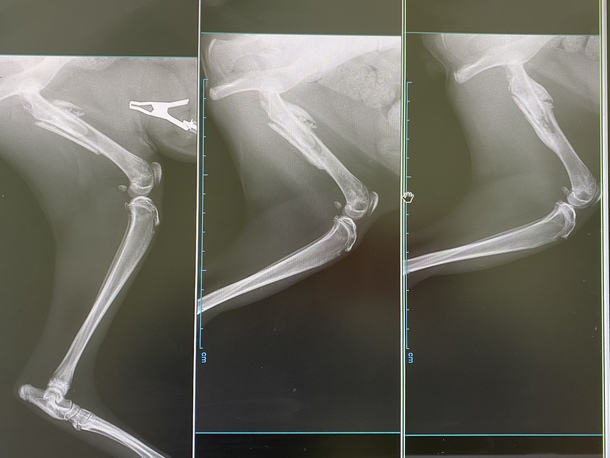

レントゲン写真

一番左がピンの除去手術をした直後、2枚目が3週間前、そして一番右が現在の骨の状況です🦴

割れてしまった所が、くっついて太くなっているのがわかります。先生曰く、骨は短くなってしまったけれどその分太く、そして強くなったとのこと💪